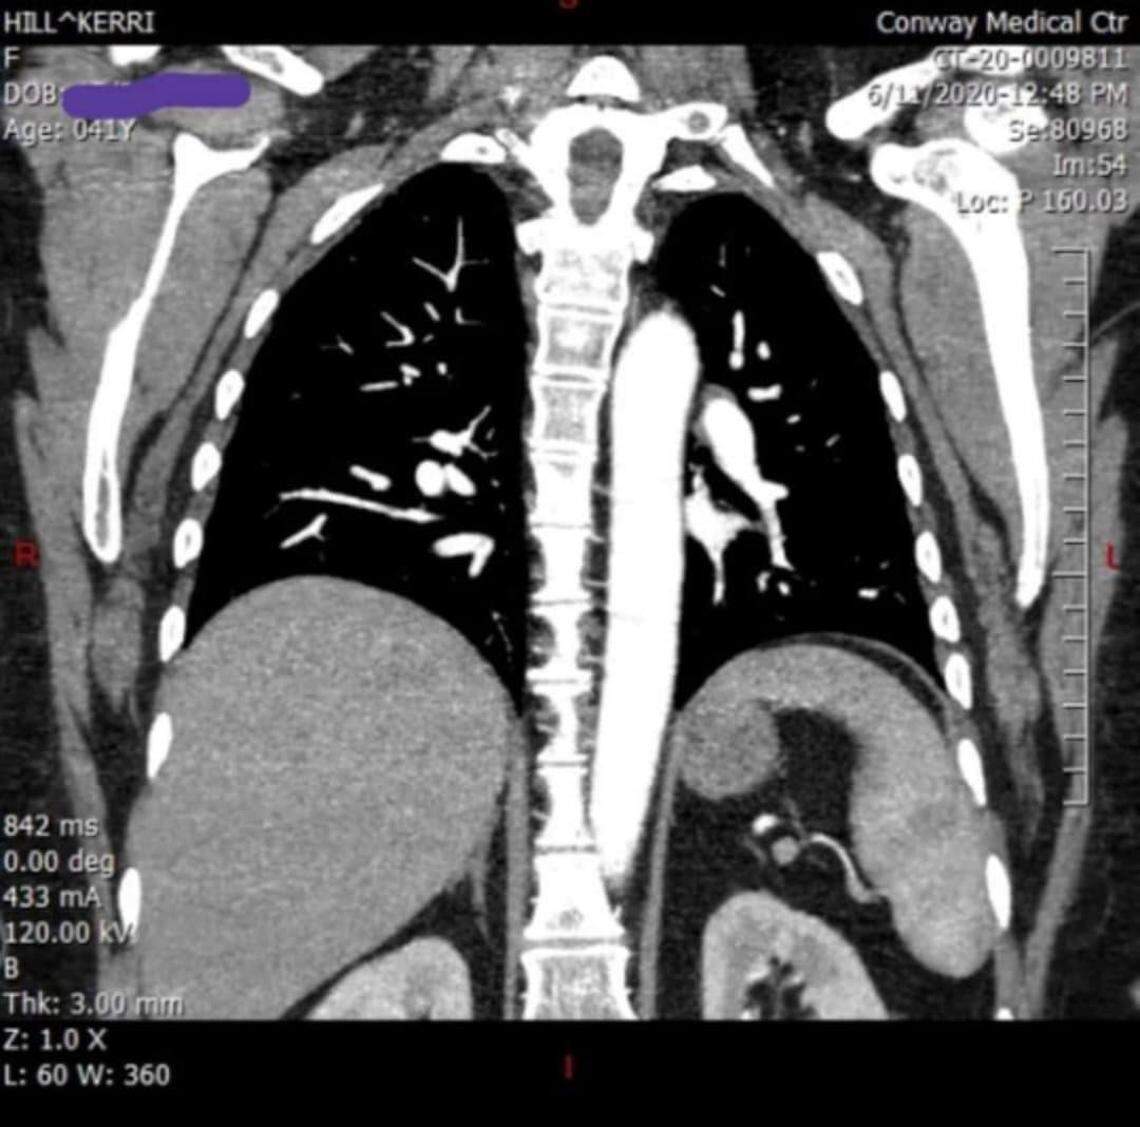

And her lungs have been scarred, a tell-tale sign of COVID-19.

Kerri Hill, 41, of Galivants Ferry, South Carolina, suffered lung damage due to COVID-19, she said. Hill contracted SARS-CoV-2 in late March, more than 180 days ago.

Kerri Hill, 41, of Galivants Ferry, South Carolina, suffered lung damage due to COVID-19, she said. Hill contracted SARS-CoV-2 in late March, more than 180 days ago. Photo courtesy of Kerri Hill